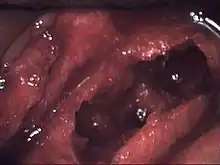

Lésions histopathologiques

Les personnes ayant une ostéonécrose de la mâchoire peuvent présenter une nécrose de l’os ou de la moelle osseuse qui a été lentement asphyxiée ou privée de nutriments. L’os qui subit un déficit chronique d’apport vasculaire réagit par le développement d’une moelle fibreuse car les fibres survivent plus facilement dans des zones privées d'éléments nutritifs, soit en formant une moelle grasse nécrosée (pourriture humide), soit en formant une moelle très sèche, parfois scléreuse (pourriture sèche), ou encore un espace complètement vide dans moelle (ostéocavitation), également typique de l’ostéonécrose. La diminution du flux sanguin peut aussi être la conséquence d’un infarctus osseux, dû à la formation de caillots de sang dans les petits vaisseaux sanguins de l’os spongieux.

À la suite de nombreux accidents ischémiques des modifications pathologiques dans la moelle osseuse et les trabéculations de l’os spongieux de la mâchoire ont été documentés. Au microscope, on distingue des zones de dégénérescence graisseuse apparente et / ou de nécrose, souvent avec de la graisse provenant de la destruction de cellules adipeuses (kystes huileux) et une fibrose de la moelle (dégénérescence graisseuse réticulaire). Ces anomalies sont présentes, même si la plupart des trabéculations osseuses paraissent à première vue viables, matures et d’aspect normal, mais à y regarder de plus près, on décèle une raréfaction localisée des ostéocytes et des micro-fissures d’étendue variable (disséminées le long des plans de clivage naturels). Les caractéristiques microscopiques sont similaires à celles des accidents ischémiques ou ostéonécroses aseptiques des os longs, des ostéonécroses induites par les corticoïdes, et l'ostéomyélite de la maladie des caissons (« plongeurs en eau profonde») [5].